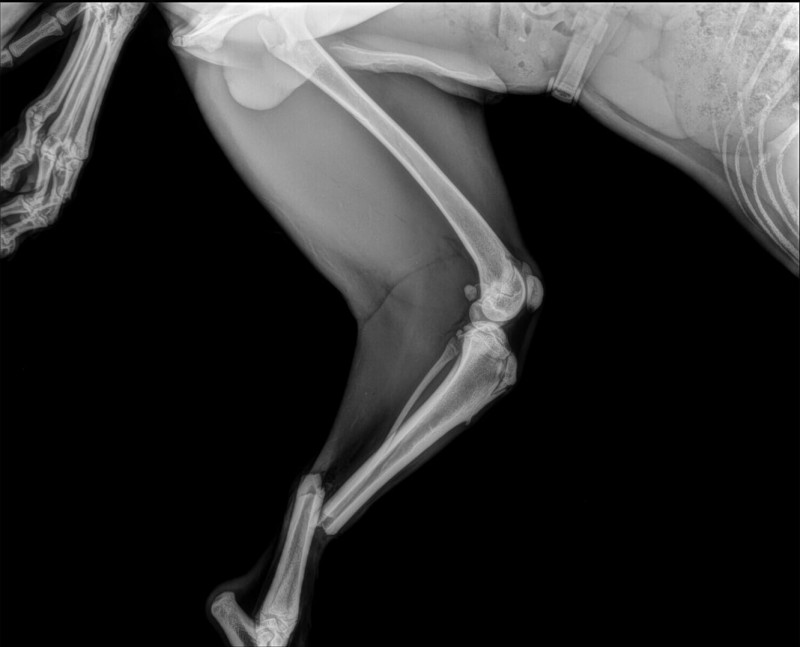

Des nouvelles de notre MERLIN au 16.12.2024 :

Patte arrière gauche

*****

Patte avant gauche